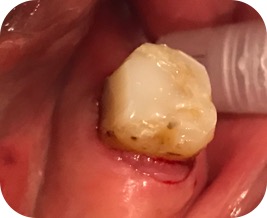

Se retira todo el

tejido cariado, se restaura el diente utilizando ácido, adhesivo universal y

composite fluido A2. Se restaura la pared lingual del 37 con ayuda de

automatrix.